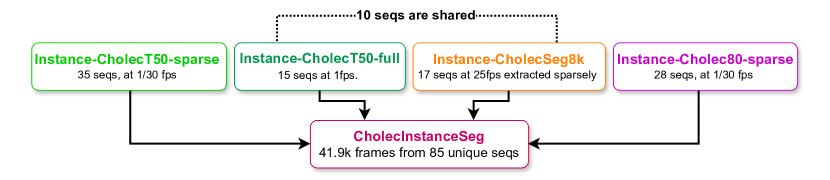

The CholecInstanceSeg dataset is curated using frames extracted from three existing laparoscopic cholecystectomy datasets: Cholec80 [12], CholecT50 [13], and CholecSeg8k [11], containing a total of 85 image sequences. These datasets are publicly available subsets of the in-house Cholec120 dataset [15] from the CAMMA research group at the University of Strasbourg. The interrelation between these datasets is illustrated in Figure 1.

Summary of CholecInstanceSeg Partitions

CholecInstanceSeg, which contains 41.9k frames from 85 unique image sequences, can be partitioned into four distinct sections based on the data source: Instance-CholecSeg8k, Instance-CholecT50-full, Instance-CholecT50-sparse, and Instance-Cholec80-sparse.

Instance-CholecSeg8k: For the 8,080 frames over 17 sequences provided in CholecSeg8k, we utilized all the images in this dataset.

Instance-CholecT50-full: For 15 sequences within CholecT50(CholecT50-full), we utilized all frames provided by CholecT50.

Instance-CholecT50-sparse: For the remaining 35 sequences in CholecT50(CholecT50-sparse), we sampled these sequences by selecting one frame out of every 30 frames ( fps), ensuring a minimum of 50 frames in each sequence.

Instance-Cholec80-sparse: We extracted 28 videos from Cholec80, which are not included in CholecT50 and CholecSeg8k, and sampled these videos at fps, ensuring a minimum of 50 frames in each sequence.

A visual representation of dataset partitions in CholecInstanceSeg can be seen in Figure 2.